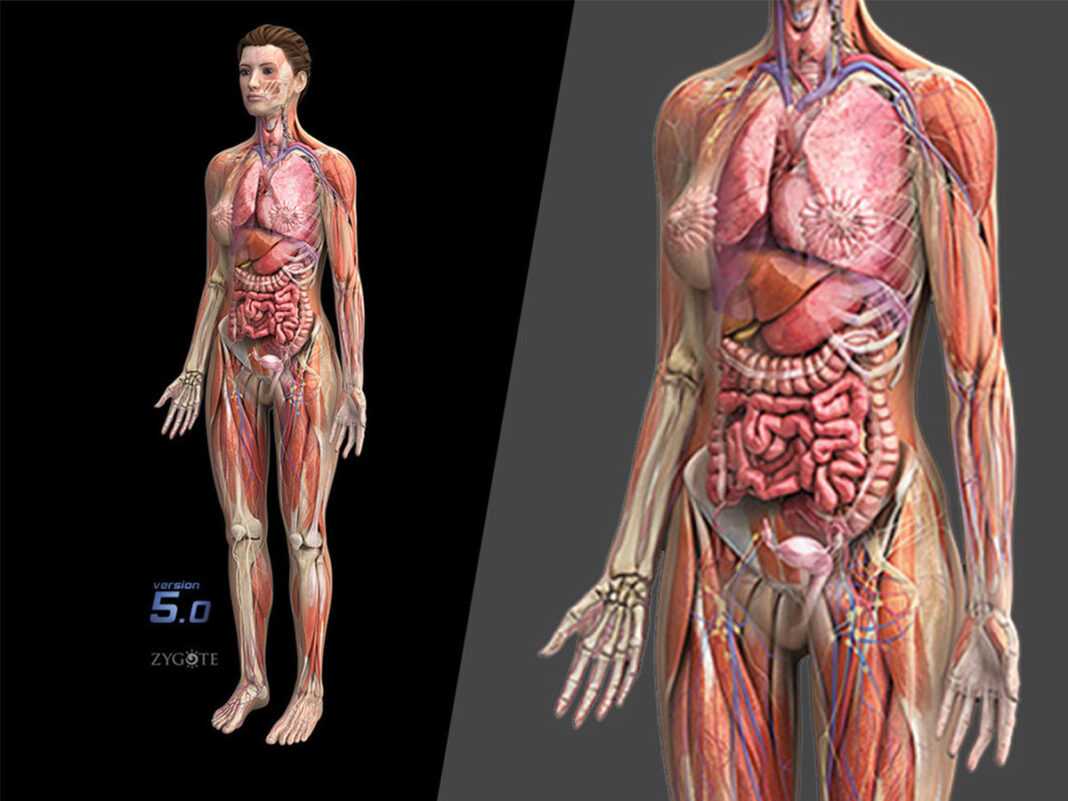

Ιατρική Εταιρεία: Η Elsevier λέει ότι το μοντέλο της μπορεί να βελτιώσει την εκπαίδευση των μελλοντικών γιατρών και τα αποτελέσματα για τις γυναίκες ασθενείς Η Elsevier παρουσίασε «το πιο προηγμένο τρισδιάστατο πλήρες γυναικείο μοντέλο που ήταν ποτέ διαθέσιμο», σύμφωνα με ένα πρόσφατο δελτίο τύπου. «Είναι η πρώτη φορά που ένα γυναικείο μοντέλο έχει κατασκευαστεί με αυτό το επίπεδο λεπτομέρειας στο σύνολό του, για να αντιπροσωπεύει το θηλυκό — αντί να αντικαθιστά συγκεκριμένες περιοχές της ανδρικής ανατομίας με γυναικεία χαρακτηριστικά», αναφέρει η ανακοίνωση της Elsevier.

Η εταιρεία, η οποία είναι γνωστλη ηγέτης στη δημοσίευση έρευνας και ανάλυσης πληροφοριών, είπε στην έκδοση ότι αυτό το μοντέλο θα βοηθήσει τους εκπαιδευτικούς για πρώτη φορά να διδάξουν, να οπτικοποιήσουν και να επεξεργαστούν την ανατομία εξ ολοκλήρου από τη γυναικεία οπτική, χρησιμοποιώντας ένα ρεαλιστικό λεπτομερές τρισδιάστατο μοντέλο.

Η Elsevier λέει ότι το τρισδιάστατο γυναικείο μοντέλο της περιλαμβάνει τις ακόλουθες σαφείς διαφορές από τα μοντέλα ανδρικής ανατομίας: Το σκελετικό σύστημα θα προσαρμόσει τις αλλαγές που αντικατοπτρίζουν τις οστικές γωνίες που παρατηρούνται συνήθως στο θηλυκό και θα δείξει διαφορές σε περιοχές που διαφέρουν από τους άνδρες, συμπεριλαμβανομένης της λεκάνης και του κρανίου

Ακριβής απεικόνιση των μυών. Ο συνολικός όγκος μυϊκής μάζας για κάθε μυ μειώθηκε κατά περίπου 30%, με βάση τα ευρήματα της έρευνας που συγκρίνουν τα δημογραφικά στοιχεία ανδρών και γυναικών.

Οπτικά λεπτομερείς περιοχές ειδικές για γυναίκες. Οι ειδικές για τις γυναίκες περιοχές είναι εξίσου λεπτομερείς με αυτές του αρσενικού.

Η απελευθέρωση ανέφερε ότι ο ιστός του μαστού μπορεί να είναι ημιτομή ή τετράγωνος για να επιτρέψει στον μαθητή ή τον εκπαιδευτή να δει τους υποκείμενους ιστούς με πιο ακριβή κατανομή και αναπαράσταση των μαστικών αδένων, που τώρα εμφανίζονται ως μη θηλάζοντες, σε αντίθεση με τους περισσότερους ανατομικούς πόρους.

Τα αναπαραγωγικά όργανα από τα εσωτερικά και εξωτερικά γεννητικά όργανα έχουν επίσης αναδιαμορφωθεί Συγκριτική λειτουργικότητα. Η έκδοση ανέφερε ότι οι χρήστες μπορούσαν να αλλάξουν μεταξύ ανδρικών και γυναικείων μοντέλων για να επιτρέψουν τις συγκρίσεις στις διάφορες δομές και συστήματα.